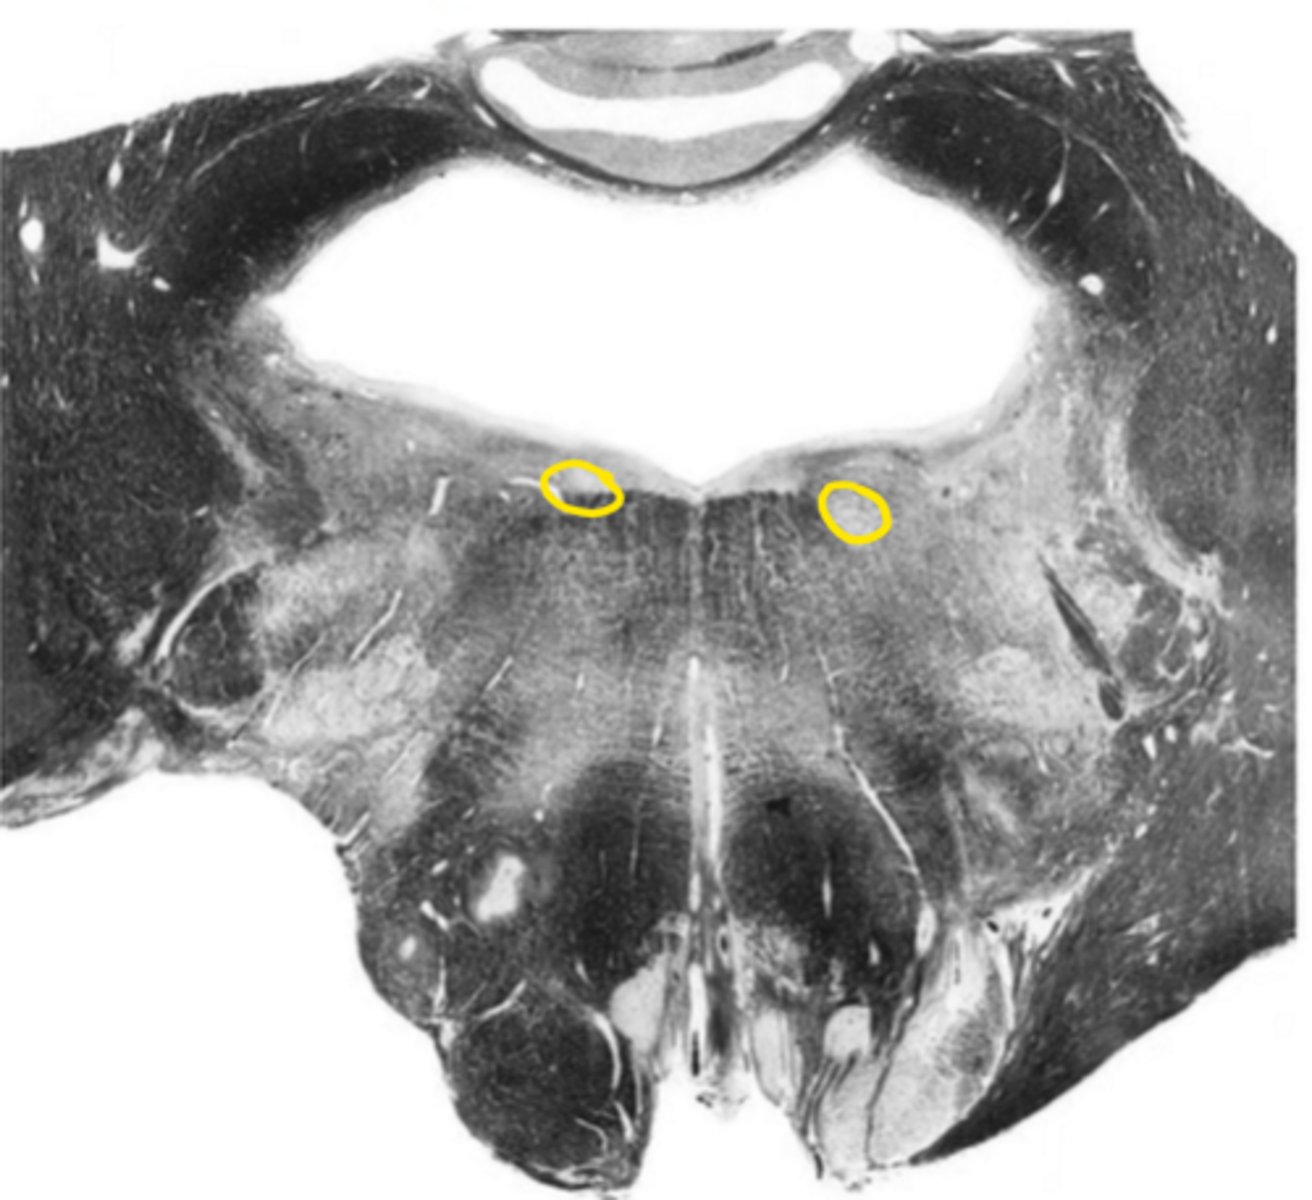

posterior median sulcus

ID the structure

hypoglossal nucleus

ID the nucleus

central gray

gracile nucleus

posterior intermediate sulcus

cuneate nucleus

ID the light area

cuneate fasciculus

ID the dark area

internal arcuate fibers

medial lemniscus

principle olivary nucleus

corticospinal fibers

anterior median sulcus

gracile fasciculus

posterior lateral sulcus